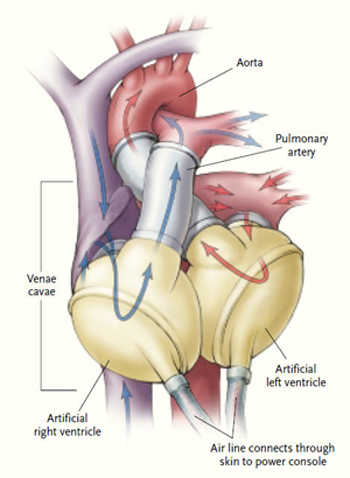

1982年12月2日

William DeVries医生第一次尝试植入人工心脏,病人是一名61岁的充血性心力衰竭的患者。尽管手术本身很成功,但是术后的处理却异常困难,以至于在1990年,该型号的人工心脏被停用。因为人工心脏可以缓解心脏移植供体的不足,故而对其的研发从未中断。许多年之后,这个1982年的研究的价值才被发觉。